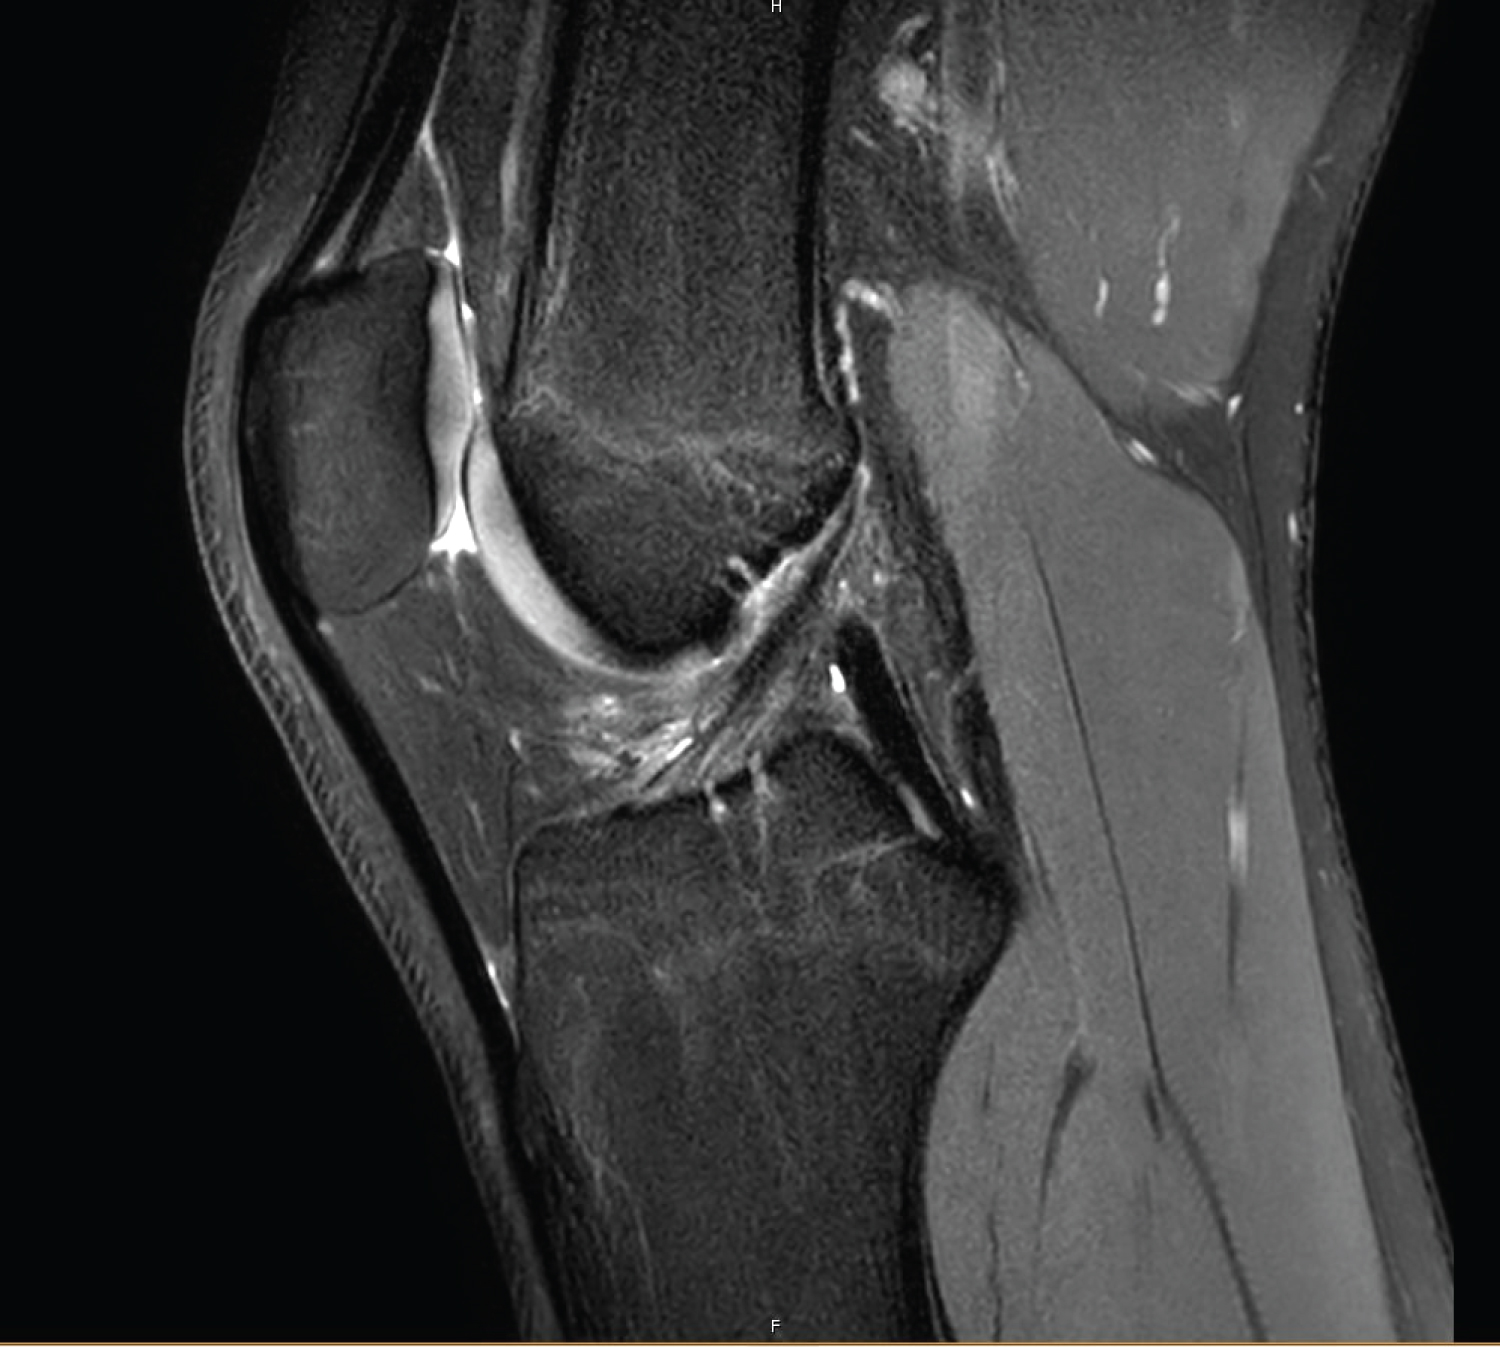

As suspected based on the clinical findings, MRI confirmed pathology involving the biceps femoris tendon, albeit a full thickness partial width tear of the posterior fibular attachment involving approximately 30% of the tendon width. This was associated with a bleed extending superior to the musculo tendinous junction (Figure 1 and Figure 2).

Figure 2: Axial PD-weighted SPAIR image of partial width tear of the posterior biceps femoris fibular attachment and bone bruising around posteromedial tibial plateau area. View Figure 2